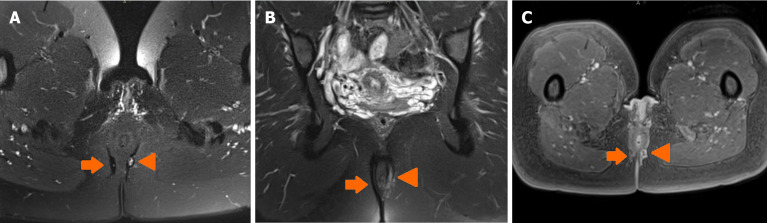

Perianal fistulising Crohn's disease is a challenging complication that can affect up to 20% of patients with Crohn's disease and is associated with significant morbidity. Despite advances in medical therapies, particularly anti-tumor necrosis factor agents, the majority of patients still require surgical intervention. Accurate diagnosis and monitoring are essential to optimise outcomes and guide multidisciplinary management. Although clinical scoring systems such as the perianal disease activity index are widely used, their subjective application limits their reproducibility and reliability, underscoring the need for more objective methods of evaluating perianal fistulising Crohn's disease activity. Imaging has thus become central to the objective assessment of perianal fistulising Crohn's disease, with magnetic resonance imaging (MRI) recognised as the gold standard in view of its ability to provide clear, detailed images of the perianal region in a radiation-free manner. Guidelines also endorse the use of imaging modalities such as endoanal ultrasound and transperineal ultrasound as viable alternatives to MRI for the assessment of perianal fistulising Crohn's disease in centres with appropriate expertise. This article aims to evaluate and compare the diagnostic accuracy and clinical utility of MRI, endoanal ultrasound, and transperineal ultrasound in the assessment of perianal fistulising Crohn's disease, highlighting their respective strengths, limitations, and roles in clinical practice.